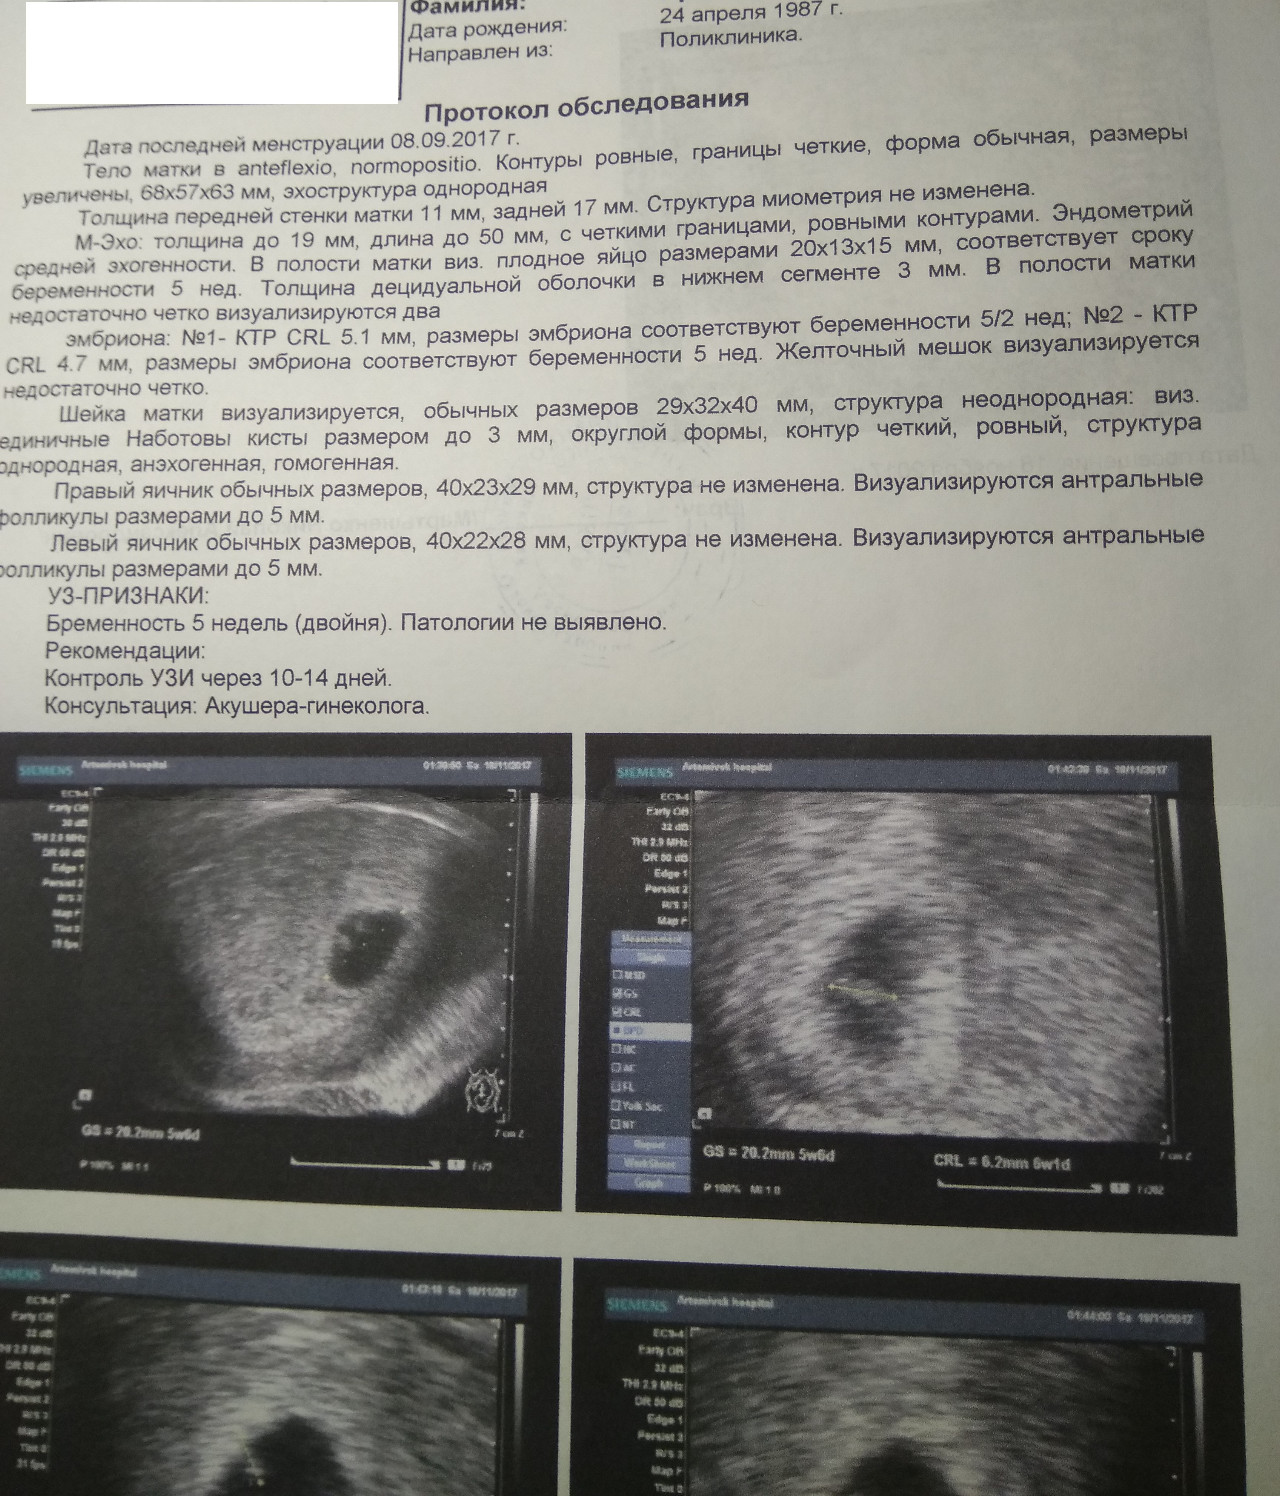

Фотографии на ранних этапах беременности

Раздел: Визуальный дайджест